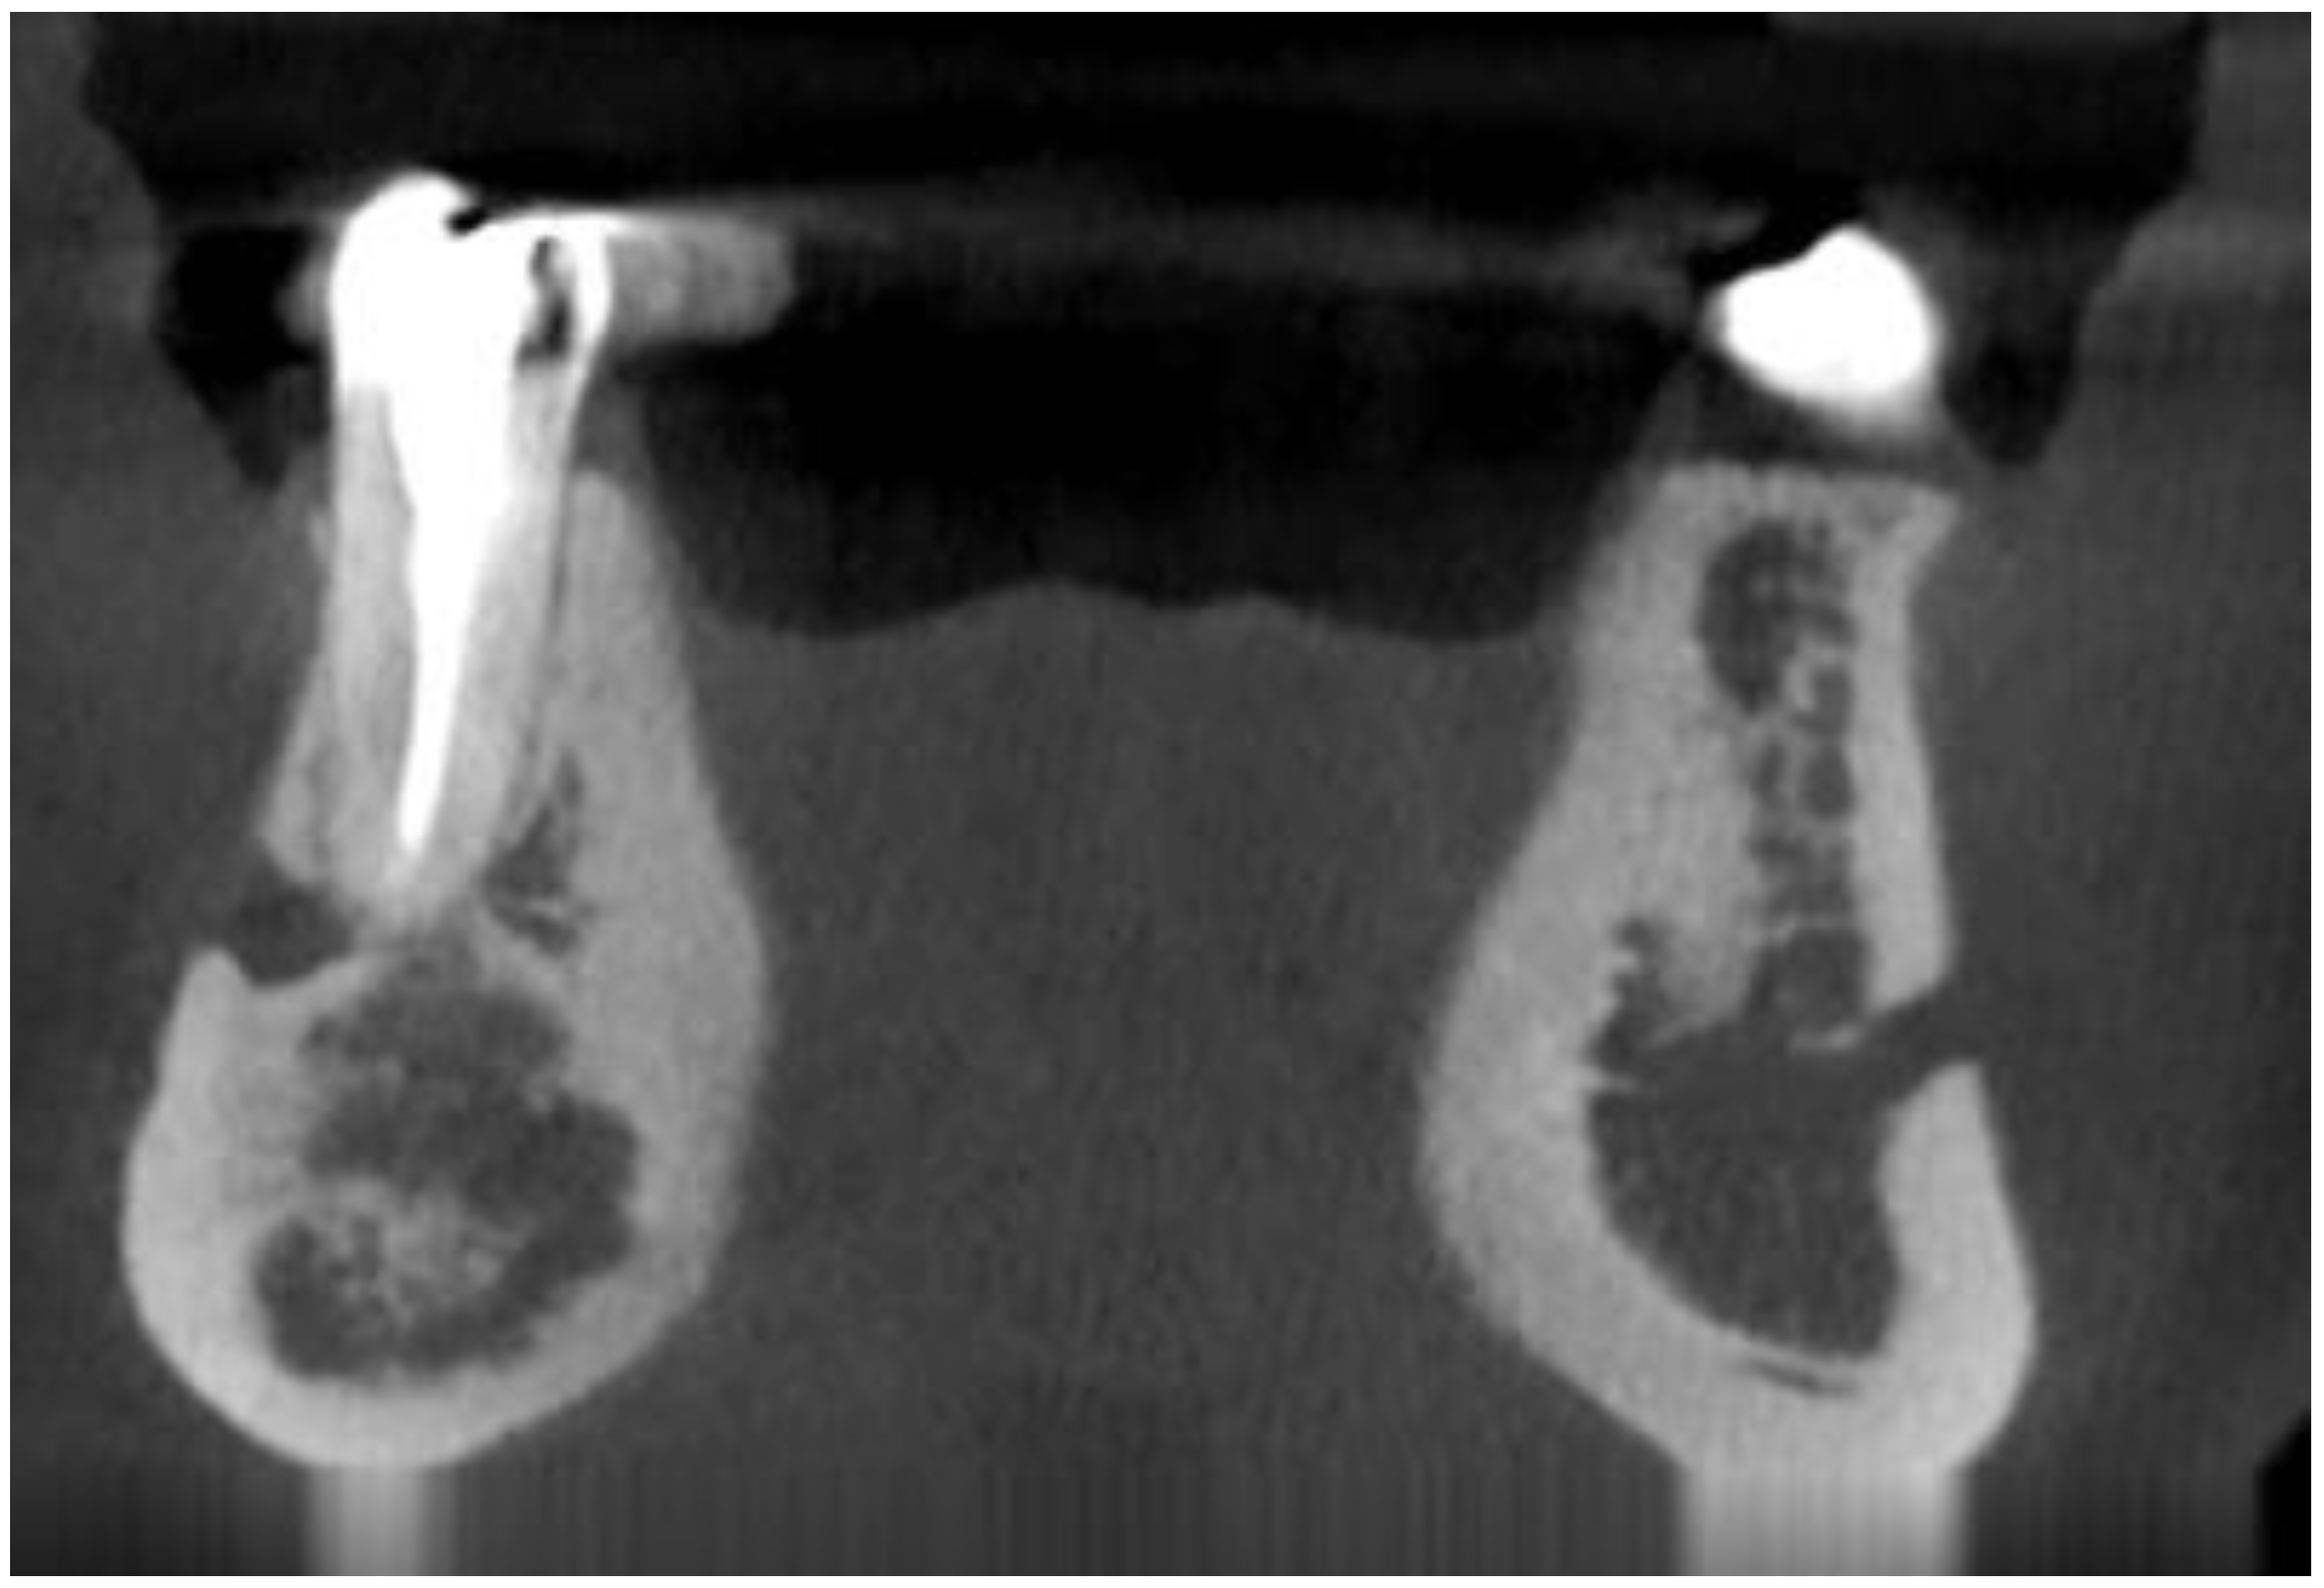

- radiolucent with/without radio-opacities with thin radiolucent rim, Figure 2

- associated with anterior/posterior teeth (Figure 2)